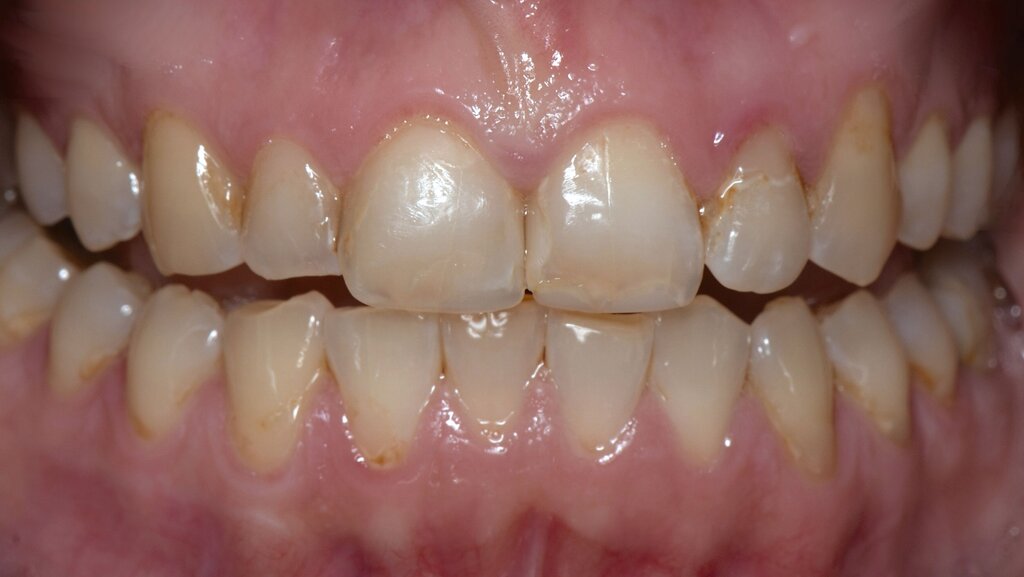

In der extraoralen Untersuchung zeigte sich ein trockenes Hautbild ohne weitere Auffälligkeiten. Intraoral waren multiple initiale Läsionen, eine erhöhte Plaqueakkumulation, sowie diverse Kompositrestaurationen im Seitenzahnbereich auffällig (Abbildungen 2a und 2b).